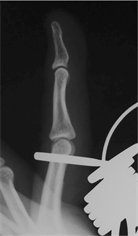

measurements. The minimum number of the ring gauge size that allowed the IP thumb joint and PIP finger joints, from the index finger to the little finger, to pass through was recorded. The positions that were actually measured by the ring gauges were the site at which weak resistance occurred (Figure 2(a)), the site at which maximum resistance occurred (Figure 2(b)) and the site at which resistance was attenuated (Figure 2(c)) when the finger was inserted into the ring. We measured the point at which there was maximum resistance, i.e. at Figure 2(b). RG was defined as the ring gauge number with the same diameter as the circumference of the IP thumb joint and PIP finger joints from the index finger to the little finger.

(a) (b) (c)

Figure 2. Measurement position for the ring gauge, (a) Distal end causing resistance; (b) Position at which maximum resistance occurs; (c) Position has passed the proximal part of the PIP.